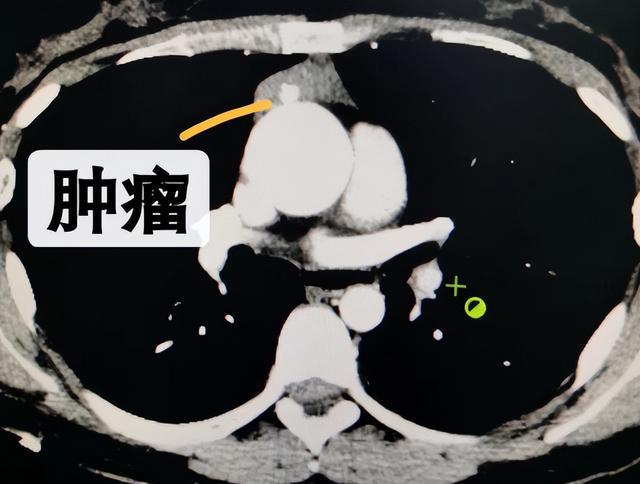

CT检查发现肿瘤

段叔叔,男,56岁,几个月前出现吞咽困难、眼睑下垂、四肢乏力、睁眼困难,四处求医未果。近日他慕名来到郴州市第一人民医院东院胸部肿瘤外科就诊,经过检查,发现纵隔肿瘤占位,有着丰富临床经验的马忠厦博士根据患者临床表现和CT检查结果诊断为:胸腺瘤合并重症肌无力,并组织相关专业团队进行MDT讨论。